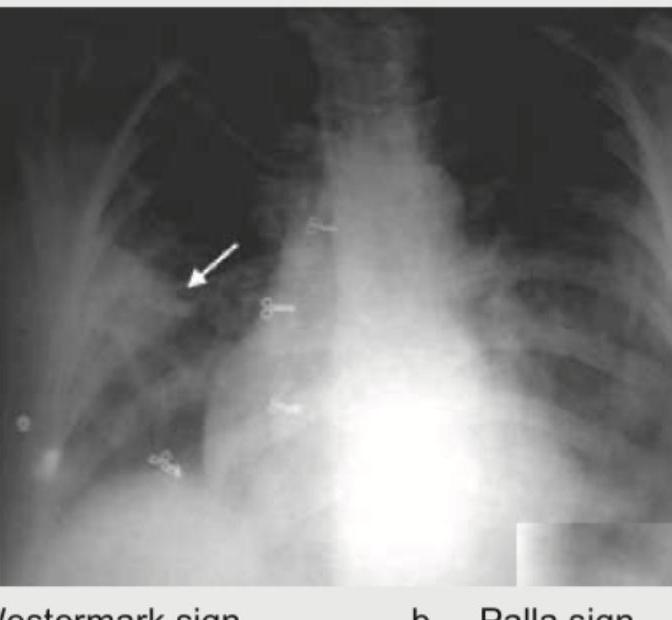

Explanation: ***Westermark sign*** - This image displays a **dilated pulmonary artery proximal to an area of oligemia**, specifically noted in the upper right lung field, as indicated by the arrow. This finding is characteristic of the **Westermark sign**, which is suggestive of a **pulmonary embolism**. - The Westermark sign represents **distal collapse of the pulmonary vasculature** due to a reduction in blood flow, making the lung parenchyma appear unusually lucent compared to adjacent normal lung fields. *Palla sign* - The Palla sign refers to a **dilated right descending pulmonary artery** (interlobar artery) on a chest X-ray. While it is also associated with pulmonary embolism, the image prominently shows oligemia, the defining feature of the Westermark sign, not solely an enlarged artery. - This sign indicates **increased pulmonary artery pressure** due to the embolus, but the key feature in the provided image is the reduced vascularity distally, not just the proximal vessel size. *Hampton hump* - A Hampton hump is a **wedge-shaped pleural-based opacity** with a rounded convex border facing the hilum. - It results from a **pulmonary infarction** due to a large pulmonary embolus and is not visible in this image. *Round pneumonia* - Round pneumonia is a **circular or oval-shaped consolidation** that is typically seen in children and appears as a mass-like lesion. - It is an infectious process with consolidation of lung tissue and does not involve vascular abnormalities like oligemia, which is clearly depicted in the image.